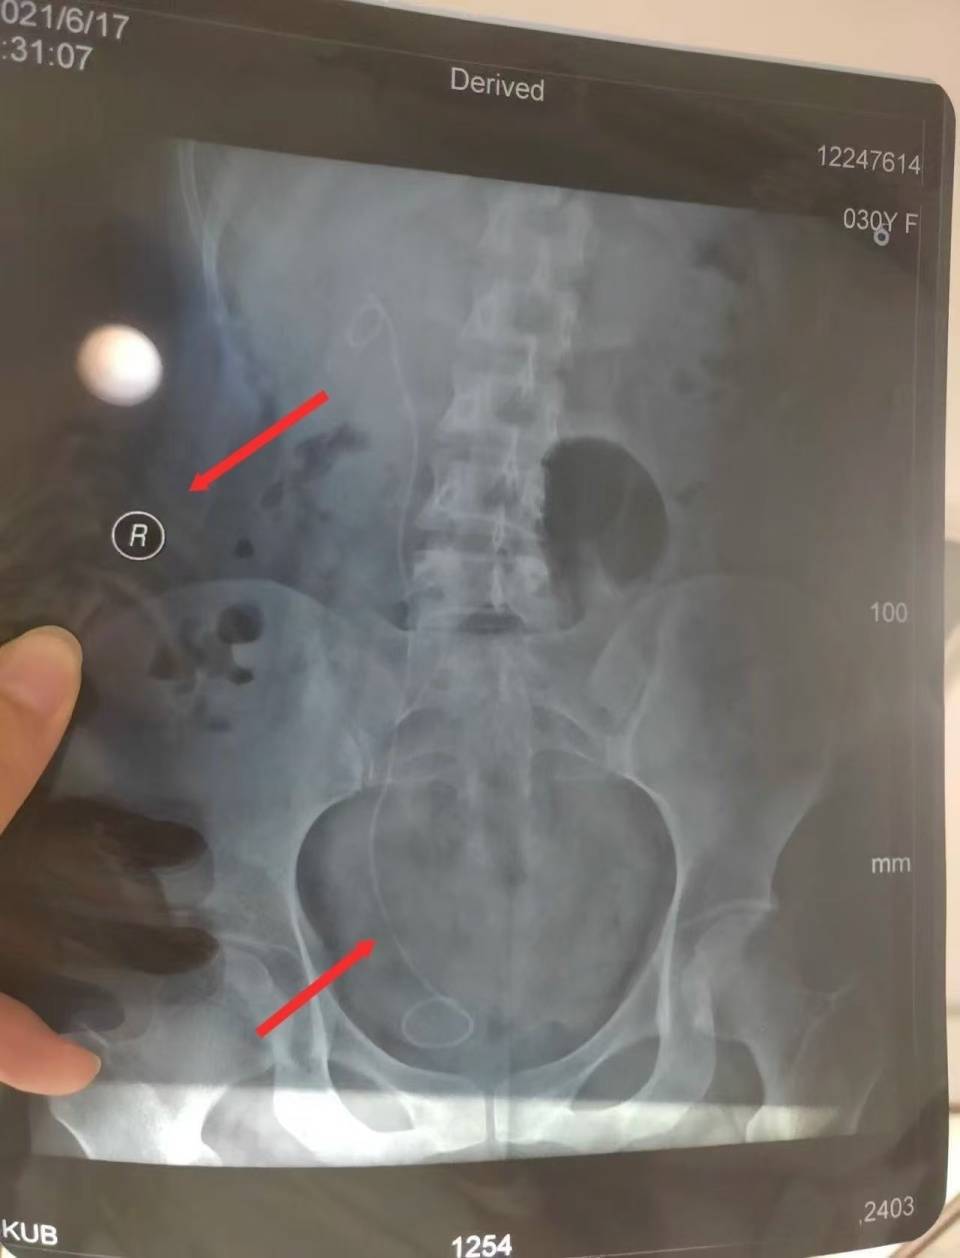

“大夫为我笃定了左输尿管手术决议,包括术前讲话以及手术知情开心书上,主刀大夫也齐是这位大夫。2021年4月21日下昼手术奏凯进行,不久后出院。”朱女士说,直到术后两个月,她到病院复查拍CT后才发现,我方蓝本健康的右输尿管内被实行了手术,患病的左输尿管反而莫得手术。朱女士提供的手术知情开心书自满,病情会诊为左侧肾盂积水伴输尿管狭小等,拟定手术为左侧输尿管镜检备推广/内切开。而在手术记录中,会诊仍为左侧肾盂积水伴输尿管狭小等,但手术称号却成了右侧输尿管推广术,右侧输尿管镜查验术。

医疗事故果决组成四级医疗事故,病院应负十足包袱

为了明确包袱,朱女士朝上海市静安区卫健委央求医疗事故果决,静安区卫健委嘱咐上海市医学会组织果决。果决答复认定,华山病院固然会诊正确,但手术决议有误,存在见告颓势。2021年4月19日,医方手术知情开心书拟定手术为“左侧输尿管镜狭小伴左肾积水”,4月21日,术中医方自行变更手术决议且依据不及(患者既往各项查验如超声、CTU、MR均教唆泌尿系病变在左侧,术后超声查验亦自满病变在左侧),术中未向患方进行见告并获得患方知情开心,术后亦未见告患方该情况,患方至6月17日门诊复查时瓦解该情况。医方见告存在颓势,在一定进度上延误了患者左侧输尿管病变第二次治愈,时代约2个月。上海市医学会以为,朱女士与华山病院医疗争议组成医疗事故。根据关联端正和条例,认定本病例属于四级医疗事故,医方承担十足包袱。